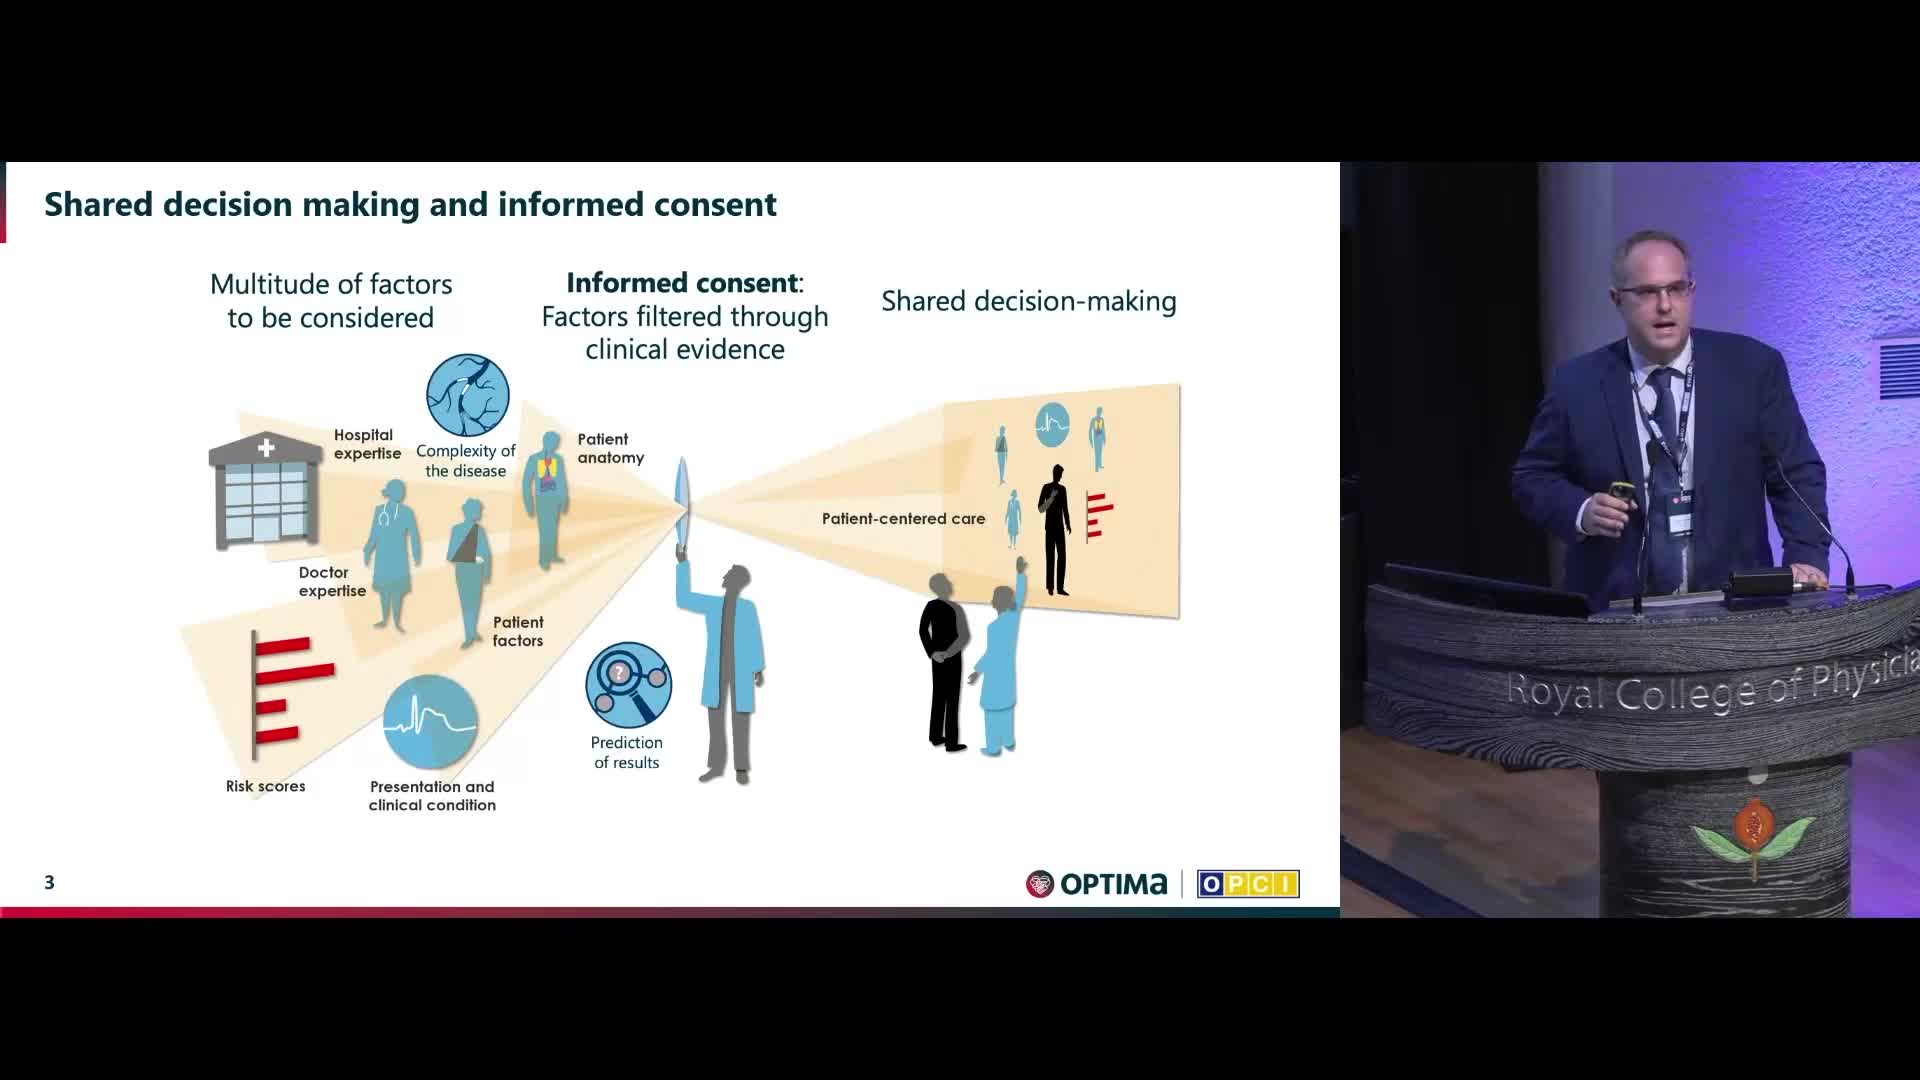

Session 1: Pre-procedure planning – are we lost without a map?